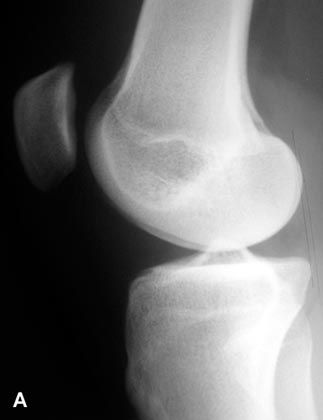

Congrès - Compte rendu Prothèses du genou difficiles de première intention : le genu valgum "sévère" , Tarik Aït Si Selmi Centre Orthopédique SANTY, 24, avenue Paul Santy, 69008 Lyon, France , Gérard Deschamps Centre de Chirurgie Orthopédique, 71640 Dracy le Fort, France N°147 - Octobre 2005 ● 7 min de lecture